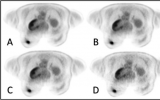

全身PET/CT可預測轉移性乳腺癌患者HER2靶向治療的療效

根據《Journal of Nuclear Medicine》9月刊上發表的一項新研究,一種新型顯像劑68Ga-ABY-025可以預測HER2陽性轉移性乳腺癌患者對人表皮生長因子受體2(HER2)靶向治療的早期代謝反應。68Ga-ABY-025 PET/CT通過對HER2表達進行全身定量分析,可在制定治療計劃中發揮重要作用,并可使患者避免不必要的藥物相關副作用。 2023-10-07

Alhuseinalkhudhur博士指出:“ 68Ga-ABY-025 PET/CT能夠提供HER2表達的全身可視化和預測代謝反應,對于轉移性乳腺癌患者來說是有利的,且超過了活檢方法。基于HER2的成像工具,可能在活檢不能安全進行或活檢結果不一致的情況下提供解決方案。此外,基于PET的方法評估靶向治療的適宜性可能有助于避免不必要的副作用,并可能為及時糾正治療提供更個性化的機會?!?/span> 2023-10-05